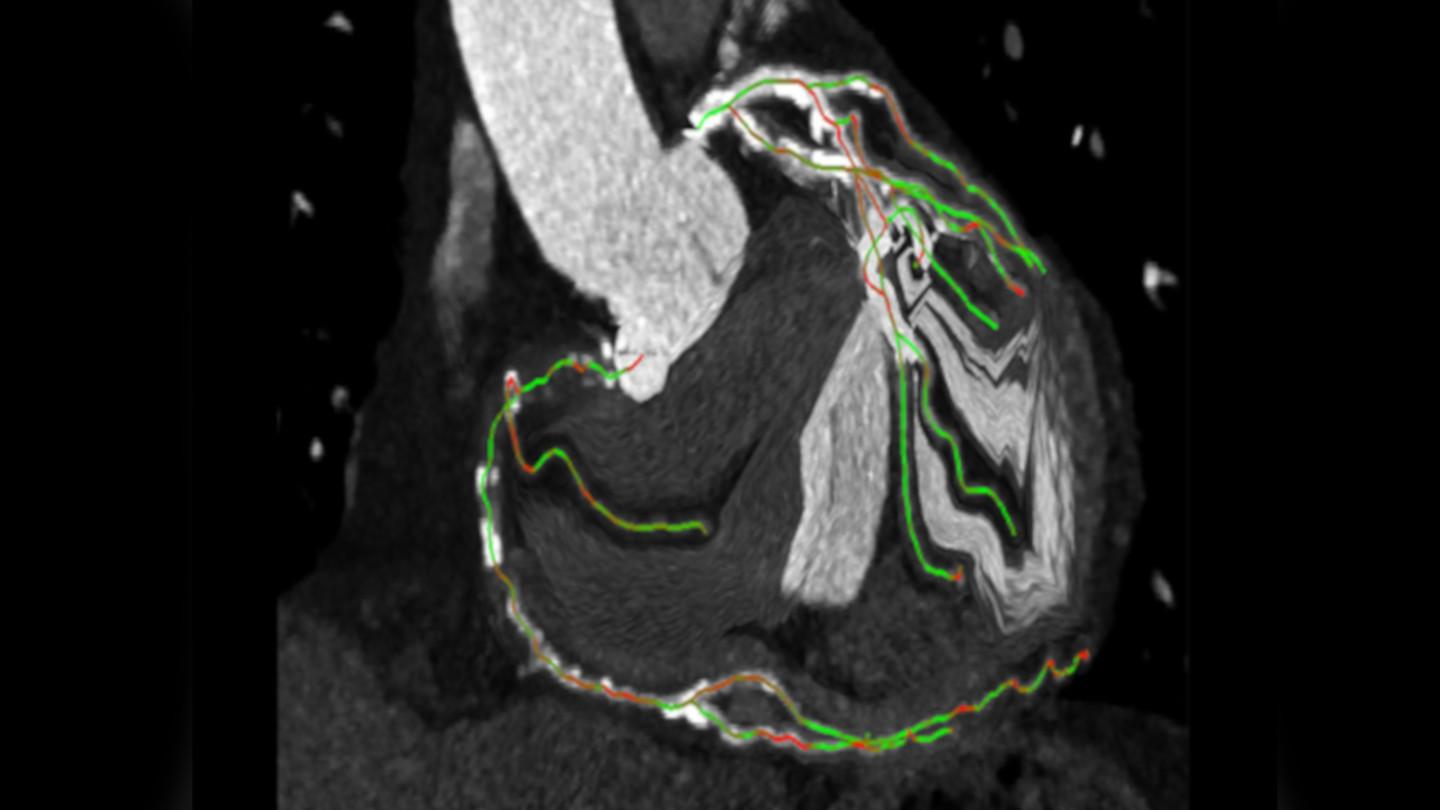

syngo CTO Guidance

Preprocedural planning using CT data

Courtesy of LMU Klinikum Munich, Germany

Expand your procedure mix by treating more CTO patients using syngo CTO Guidance for

- automated segmentation of the coronaries, centerline extraction, and color coding of the centerlines to indicate foreshortening;

- preprocedural planning of optimal angulations;

- shorter wiring times2

- reduced fluoroscopy duration2